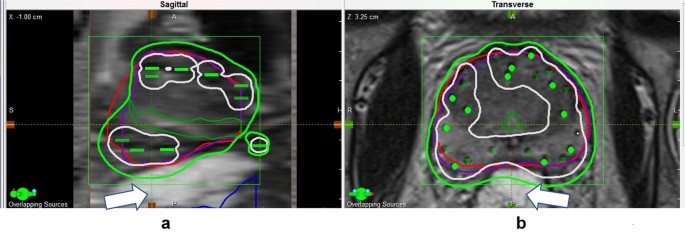

Aim: Patients of proton beam therapy (PBT) for prostate cancer had been continuously growing in number due to its promising characteristics of high dose distribution in the tumor target and a sharp distal fall-off . Considering the large number of proton beam facilities in Japan, the further increase of patients undergoing this treatment is due to the emendations by Japanese National Health . . .